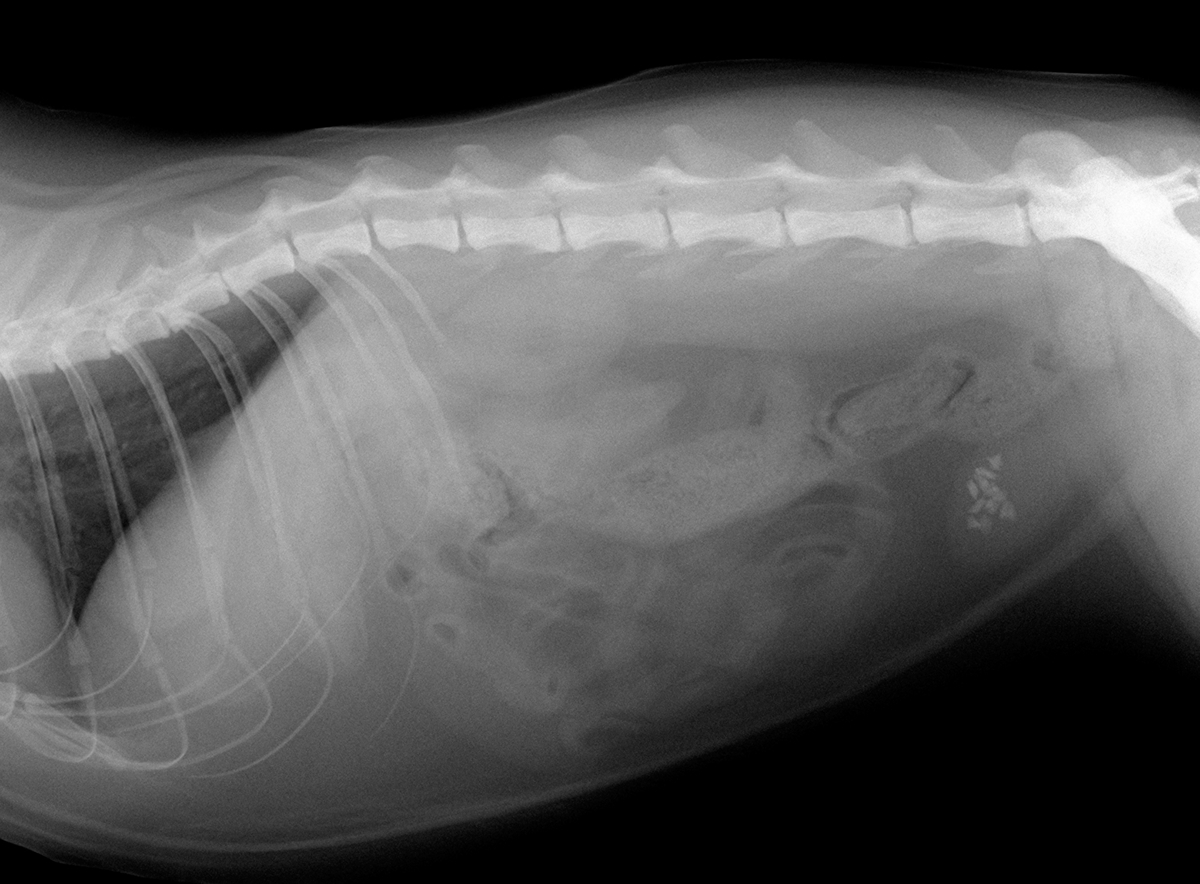

レントゲン検査において、多数の結石が膀胱内に確認されたため、『膀胱結石』と診断しました。

この子の場合は多数の結石があり、食餌療法のみでは血尿が治らないと判断し、飼い主様とご相談の上、早期に膀胱結石摘出術を行うこととなりました。

手術により膀胱を切開し、確認すると合計で11個の結石がありました。